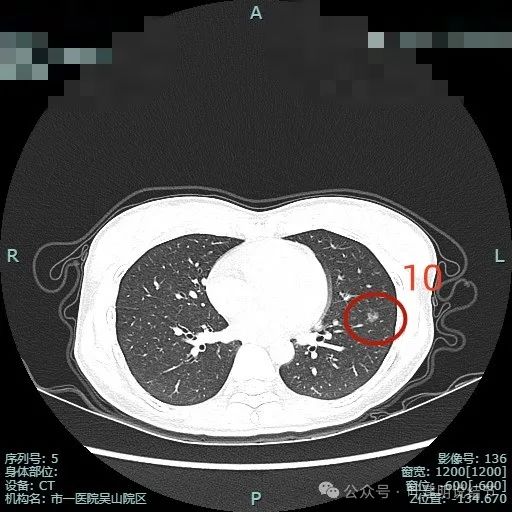

病灶10:左下叶磨玻璃结节,密度不太纯,但说不上纵隔窗可见的实性成分,表面不平,邻近叶裂,有分叶征。考虑微浸润性腺癌或浸润性腺癌贴壁为主型可能性大。